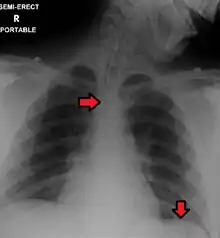

Confirming placement